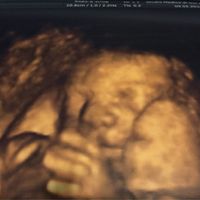

Grazie alla morfologica finalmente sappiamo che sta bene e che è un maschietto...

Ornella, Il 15 Marzo 2016 alle 21:41

Questa mattina finalmente abbiamo fatto l'ecografia morfologica... Che emozione! Il sesso c'è l'ha svelato quasi subito... E' un bel maschietto! Quello che io mi sentivo fin dall'inizio... Anche se...